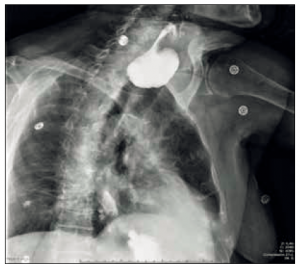

Mme C., 83 ans, fausses routes à répétition

Une femme de 83 ans est hospitalisée pour altération de l’état général dans un contexte de fausses routes à répétition évoluant depuis plusieurs années. Présentation du cas Mme C. est…